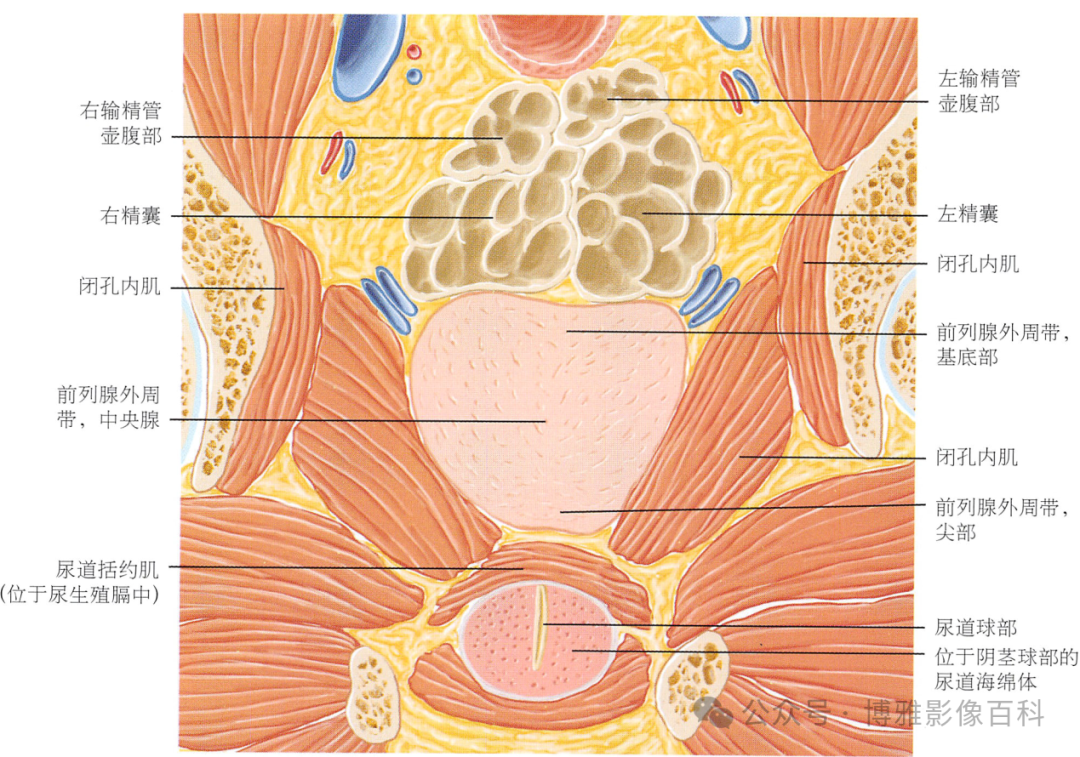

解剖学

前列腺分区解剖学

MR 解剖学